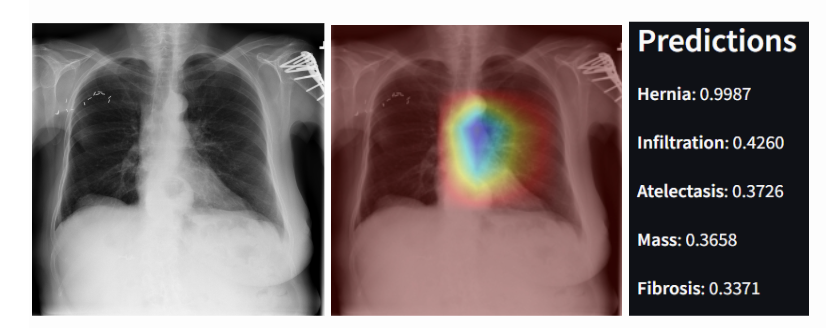

Figure 1: (Left) An example of an X-Ray from the NIH ChestX-ray14 with Hernia and Infiltration as its ground truth findings. (Center) Grad-CAM visualizations of the same X-Ray image. (Right) DACNet’s predictions of the 5 most likely findings in the image.

This is an example of an X-Ray diagnosed with both a Hernia and Infiltration. The model correctly assigns the highest probability to the correct diseases (hernia and infiltration), but it only predicts that Hernia has a probability above 50%. This behavior reflects the model’s high sensitivity (as indicated by a high AUC) but lower precision, leading to a lower F1 score. The model is good at ranking the correct disease highest, but less effective at distinguishing between the presence and absence of each disease. This observation is consistent with the trade-off between sensitivity and specificity in imbalanced datasets.